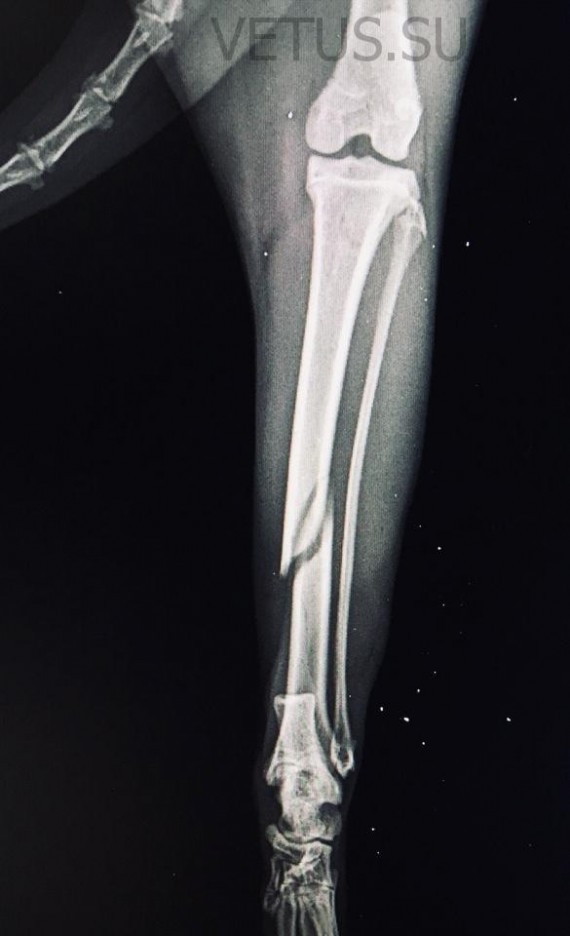

Перелом

Перелом – это нарушение целостности кости. Он сопровождается повреждением окружающих тканей. Возникают в результате травм.Чаще всего кошки ломают конечности, челюсти, ребра, хвост и таз. Закрытый перелом – кожные покровы в месте перелома не поврежденыОткрытый перелом – когда в месте перелома есть рана, из которой может быть видна кость.

Симптомы:Не могут шевелить травмированной частью телаНе могут опираться на травмированную частьБольОтекНеестественное положение части телаКровотечениеПри переломе ребер – сложно дышатПри переломе челюсти - слюнотечение

Первая помощь:Если перелом открытый – постарайтесь остановить кровь с помощью полотенца или марли. Обездвижьте травмированную часть тела.Отвезите к ветеринару.Лечение:Проводят операцию. Устанавливают специальные спицы в кости. Постепенно кости срастаются.